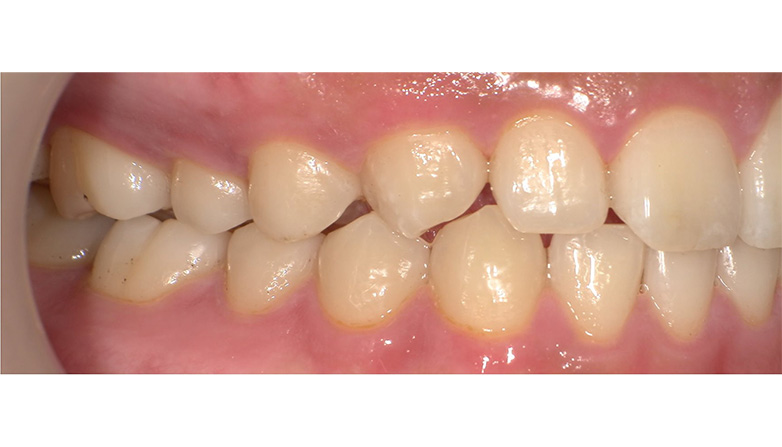

症例2

before

after

| 主 訴 | 着色を落としたい |

|---|---|

| 治療期間 | 通院 1回 |

| 治 療 費 | 1回 7,700〜11,000円(税込) |

| 治療内容 | PMTC |

| 治療のリスク | 歯自体の色を白くすることはできない。 しばらくすると再び着色することがある。 |